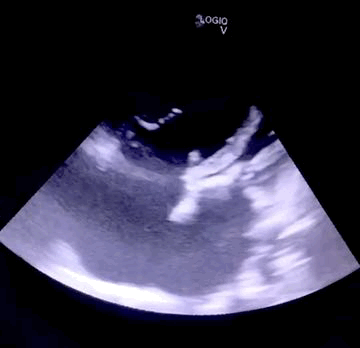

Imagem da Semana

Paciente de 60 anos, acompanhava no ambulatório de cardiopatias congênitas (perdeu seguimento). Havia recusado tratamento cirúrgico de uma CIA. E deu nisso: disfunção de VD e comprometimento do VE reflexo das altas pressões nas câmaras direitas.